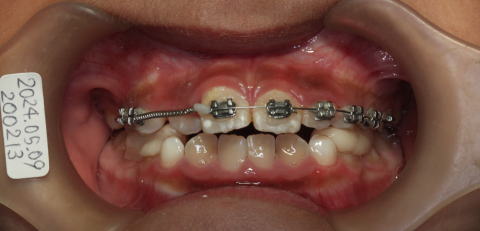

2024-05-09

12番が入る空間が出来たので咬合挙上して、21番を前に出すようにする。

12番の部分が狭いのでバネで大きくする。